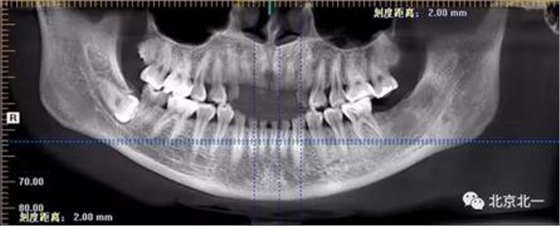

圖二:自帶的CBCT顯示下牙槽神經管貼著智齒走形。